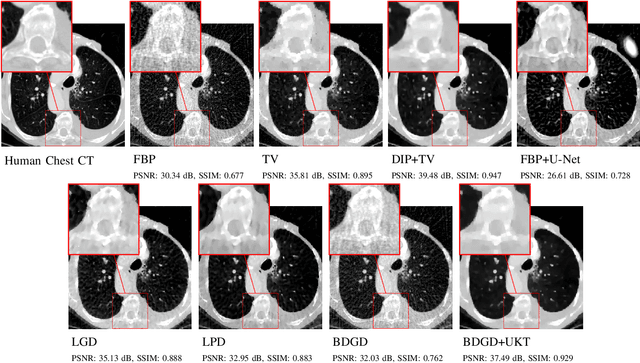

Abstract:Deep learning-based image reconstruction approaches have demonstrated impressive empirical performance in many imaging modalities. These approaches generally require a large amount of high-quality training data, which is often not available. To circumvent this issue, we develop a novel unsupervised knowledge-transfer paradigm for learned iterative reconstruction within a Bayesian framework. The proposed approach learns an iterative reconstruction network in two phases. The first phase trains a reconstruction network with a set of ordered pairs comprising of ground truth images and measurement data. The second phase fine-tunes the pretrained network to the measurement data without supervision. Furthermore, the framework delivers uncertainty information over the reconstructed image. We present extensive experimental results on low-dose and sparse-view computed tomography, showing that the proposed framework significantly improves reconstruction quality not only visually, but also quantitatively in terms of PSNR and SSIM, and is competitive with several state-of-the-art supervised and unsupervised reconstruction techniques.